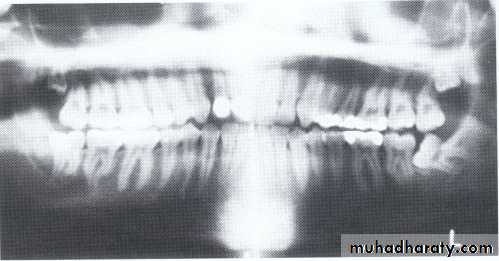

Paramolar blocking the eruption of 3rd molar.

MesiodensDistomolars(4th molar)

Distodens or distomolarParamolar